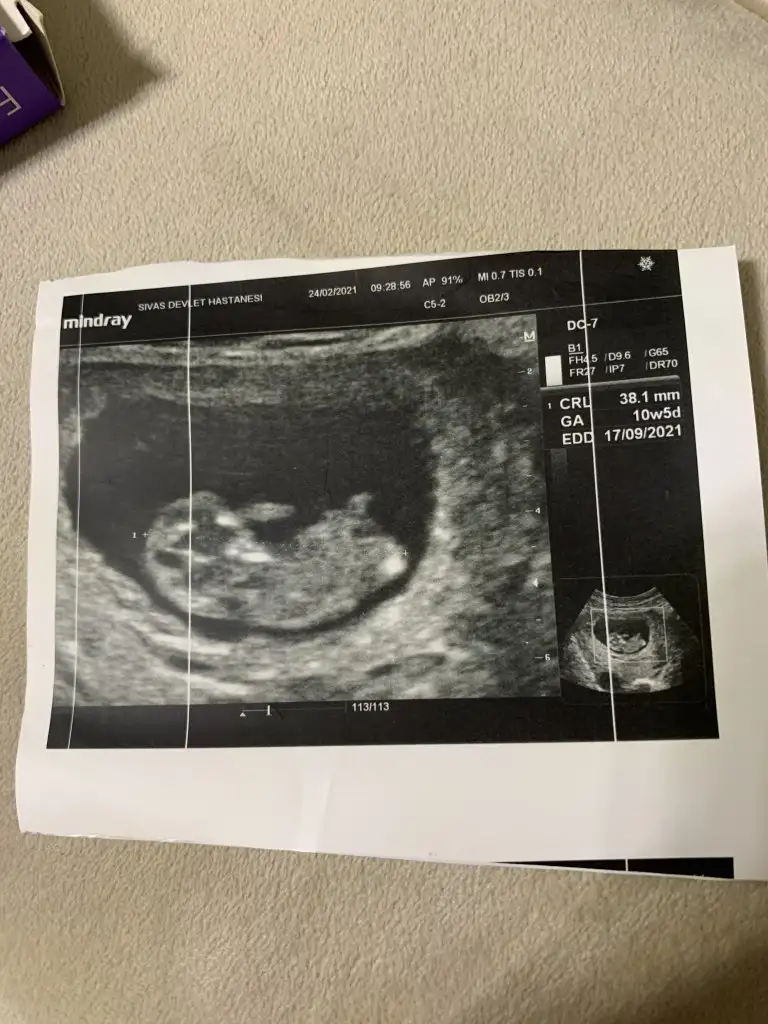

• IMG_20210224_185135.webp

IMG_20210224_185135.webp

37,5 KB · Görüntüleme: 71

Bende böyle bir şey okurmuştum bazı sayfalarda 9+4 ü 9 haftalık almış bazıları 10 haftalık 10 haftalığa baktıysan büyük görmüşündür. Bende şuan 9+4 üm 28 mm dedi gayet normal

Ay rahatladım teşekkür ederim, uygulamada da yaklaşık 4 cm diyince korktum. Size iyi dedi dimi doktorunuz